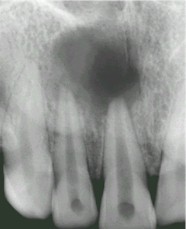

Lorsque le patient vient consulter, la pulpopathie est au stade de la nécrose pulpaire. La cavité pulpaire est remplie d'un magma purulent, l'inflammation a gagné l'espace péri-apical. Le patient présente souvent une tuméfaction vestibulaire, parfois palatine ou linguale. Quelquefois le stade d'une cellulite péri-maxillaire est atteint avec sa volumineuse tuméfaction, si spectaculaire qu'elle inquiète le patient et parfois le praticien !

Mme A. C., 47 ans, vient consulter à la demande de son médecin homéopathe. A la suite de l’extraction banale de sa première molaire inférieure droite, une alvéolite a incité son dentiste traitant à proposer une antibiothérapie. Mais à plusieurs reprises, l’arrêt de l’antibiothérapie a été suivi par une récidive = suppuration relativement peu abondante, sans signes inflammatoires marqués, et sans tendance à la cicatrisation. Cette situation durait depuis environ 6 semaines.

Sur la notion de morphologie bréviligne grasse, le manque de réactions, la frilosité avec aggravation au froid humide, la tendance lipothymique, l’obstruction nasale nocturne et la fréquence des épistaxis, l’oppression respiratoire fréquente avec palpitations lors d’un effort physique, AMMONIUM CARBONICUM 5 CH trois fois par jour a été prescrit, avec des bains de bouche au CALENDULA. Puis une 7 CH une fois par jour, puis une 9 CH un jour sur deux. La cicatrisation a été obtenue au bout de 18 jours, sans autre suite. La suppuration s’est tarie progressivement.